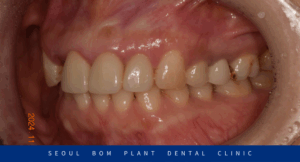

환자분께서는 40대 초반 여성분으로

위턱 오른쪽 두 번째 앞니(#12)의

파절로 인해 내원해 주셨는데요.

먼저 구강 내를 살펴보았는데요.

치아머리가 기존 보철물과 함께

잇몸 라인까지 다 부러져 나가

잇몸 위 치질 부분이 약 1~2mm 정도

남아있는 상태였습니다.

기존 보철물 안으로 2차 충치가 생기면서

약해진 치질이 강한 저작력을 버티다가

결국 파절 된 상황이었습니다.